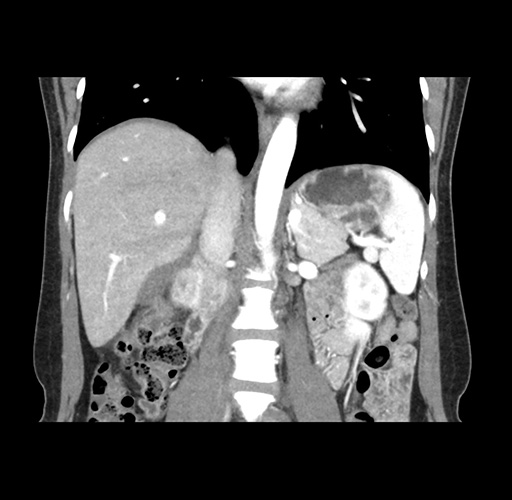

Imaging Analysis

Look through the patient's CT scan to identify any areas of concern for the necessary procedure.

Based on your CT findings, which issue(s) would give reason for "planned slowing down moment(s)" in this case?